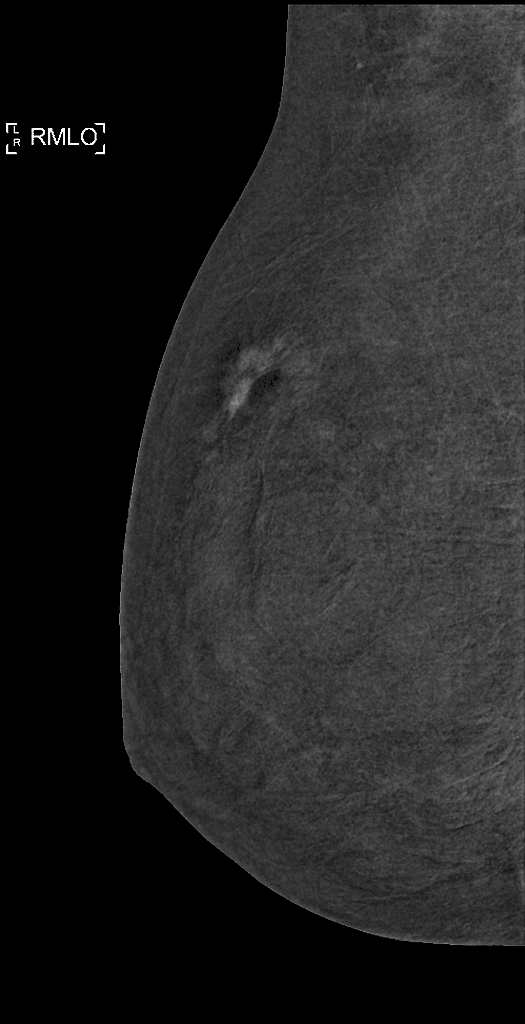

Series (5)

Oblique

Vú phải (Right breast)

- Tổn thương cản quang (radiopaque lesion), đậm đặc (dense), dạng sợi (fibrous), với bờ không đều (irregular) và dạng gai (spiculated).

- Kích thước khoảng 20 x 17 x 10 mm, ở vị trí khoảng 4 giờ vùng trong vú phải, nằm cạnh dấu chỉ điểm tam giác cản quang (radiopaque triangle marker).

- Co kéo da (skin retraction) do tổn thương, có thể quan sát thấy trên hình ảnh.

- Clip đánh dấu cản quang (radiopaque marker clip) được đặt sau khi sinh thiết lõi (core biopsy) tổn thương, nhằm đánh dấu vị trí tổn thương cho các lần sinh thiết sau.

- Không thấy hạch bạch huyết (lymph nodes) lớn.